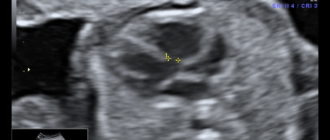

Дефект межжелудочковой перегородки. ДМЖП у плода: причины, диагностика и последствия Дефект межжелудочковой перегородки (ДМЖП)